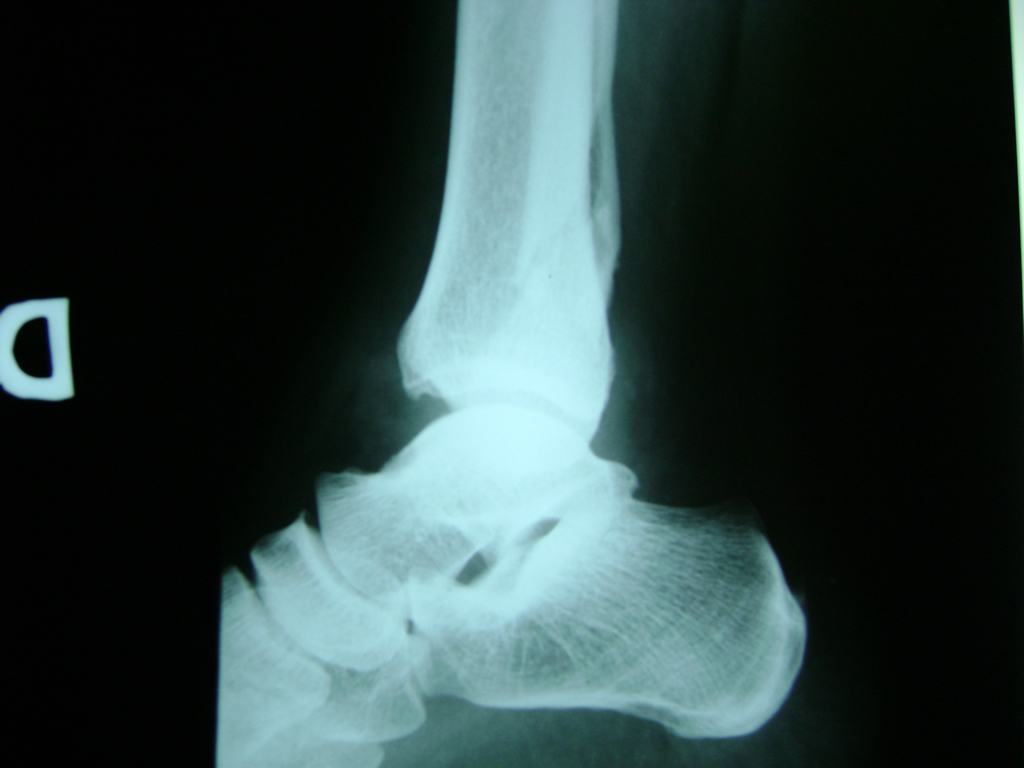

Una fractura de tobillo es la rotura de uno o más de los huesos del tobillo. Estas fracturas pueden ser:

- Producirse en uno o ambos lados del tobillo.

- Los extremos de los huesos están desalineados entre sí (desplazados).

- La fractura se extiende hasta la articulación del tobillo (fractura intra-articular).